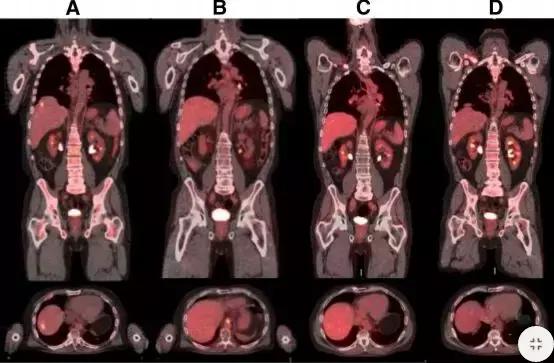

FoundationOne®检测胃癌中临床相关变异和新的靶向路径.

(一)患者检测到MET扩增(12个拷贝数),使用克唑 替尼后,肝转移消失,疾病控制达到5个月。

(二)胃癌患者检测到FGFR2扩增,患者对FGFR2*制剂抑**AZD4547有效,治疗6个月后,肝转移灶基本消失。